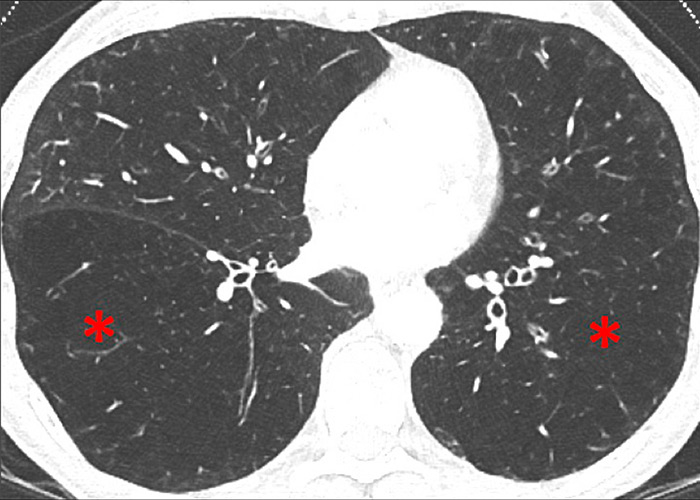

Perfusion could also be assessed with DECT in patients with PH caused by emphysema or lung fibrosis (fig. 11). The regional severity of pulmonary emphysema can be evaluated by correlating functional perfusion images with anatomical changes. Lee and coworkers found that DECT could be used for emphysema quantification and regional perfusion evaluation by use of iodine maps [45]. In emphysema, destruction of alveoli and interstitial spaces leads to a loss of pulmonary vessels, responsible for a decrease in perfusion. In lung fibrosis, perfusion defects reflect pathological processes such as small-vessel remodelling or fibrotic obliteration of the pulmonary vasculature.

Figure 11

Chronic obstructive pulmonary disease. Correlation between panlobular emphysema (A/B) and pulmonary hypoperfusion (C/D) (stars).